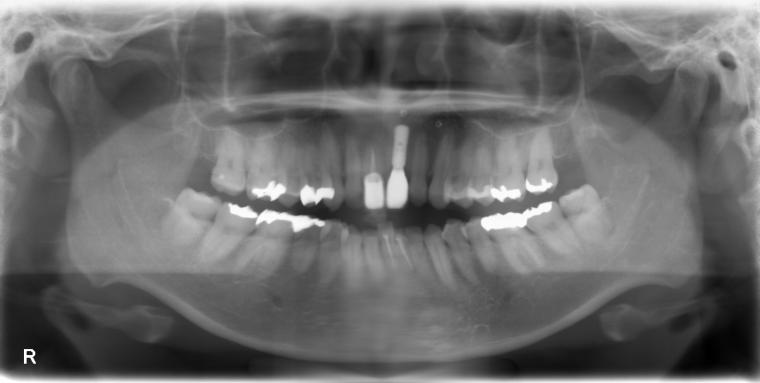

BEFORE

37歳女性/上1本欠損/インプラント埋込手術

左上前歯が脱臼した状態でご来院した患者さんです。

抜歯後に土台となる骨を作る処置の後、インプラントを1本埋入しました。